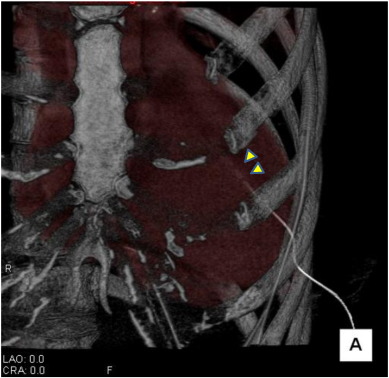

Fig. 2

Fig. 2.

Cardiac perforation revealed by non-contract 3-dimension computed tomography.

The catheter has penetrated the anterior wall in the apex of her myocardium and the tip is present in the basal portion of her left ventricle cavity. The side holes in the catheter were all present in her left ventricle cavity (arrowhead).